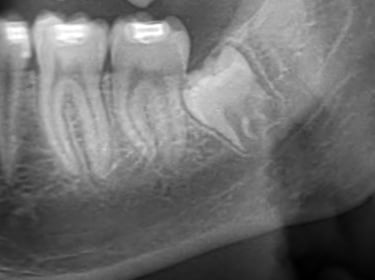

Estrazione Denti Giudizio

I denti del giudizio possono causare dolore e danneggiare i denti vicini: intervenire tempestivamente per proteggere il tuo sorriso.

Servizio Estrazione Denti

Estrarre denti del giudizio con competenza e sicurezza per il tuo benessere.